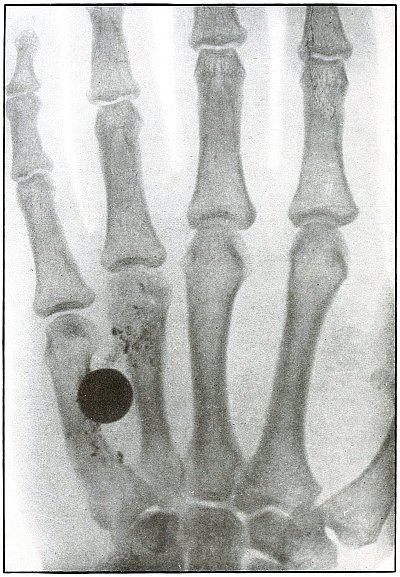

Plate 44.

[Pg 99]

Rifle—Plate 44.

UPPER EXTREMITY.

Gunshot Fracture of the Third Phalanx.

The course of the bullet was anteroposterior through the base of the

proximal phalanx of the middle finger, with a velocity of long range.

It practically punctured the bones and split off a few fragments

without displacement.

The wound of entrance would be much the same as the wound of exit,

with the latter, but a little larger.

Treatment is conservative.

[Pg 100]